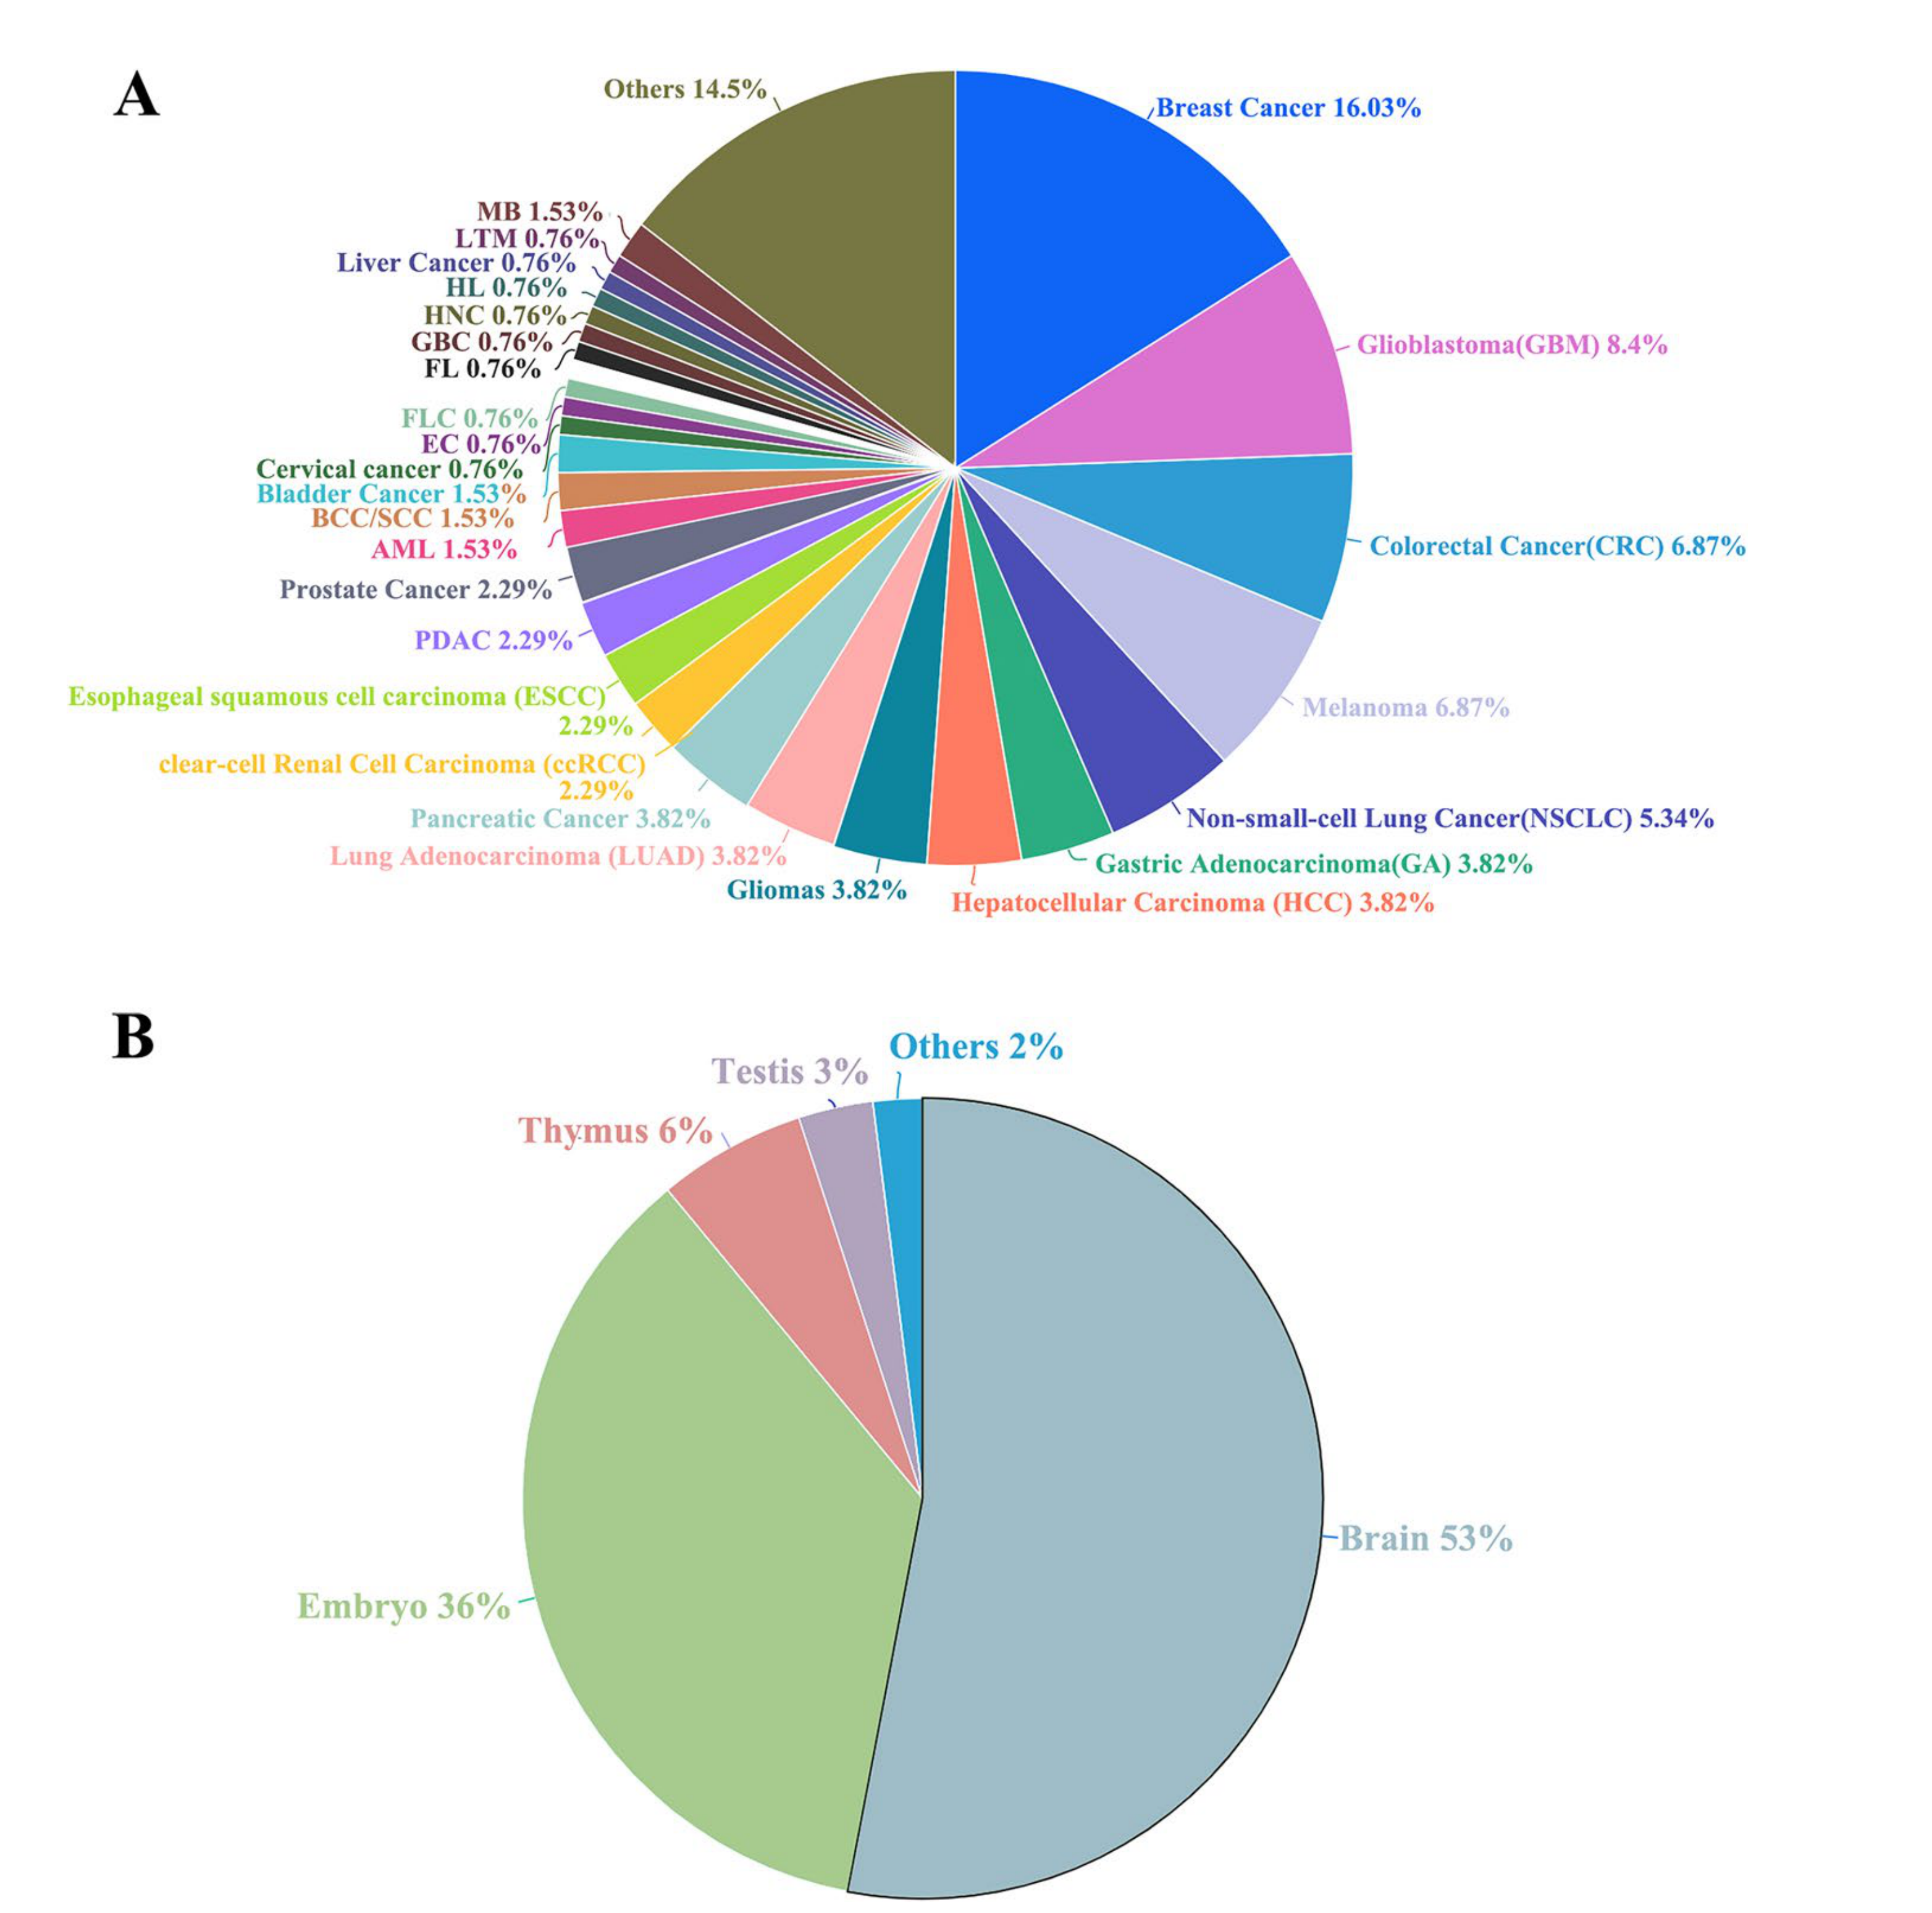

Zohora F.T. et al. - 2025

CellNEST reveals cell–cell relay networks using attention mechanisms on spatial transcriptomics

Chart Type

Pie Chart

Summay/Aggregate

Which cell types participate in different stages of a communication relay?